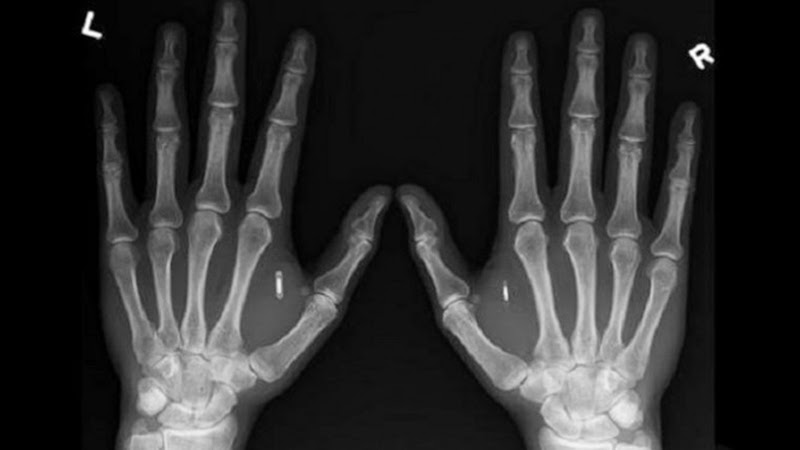

ชิป RFID นี้มีขนาดใหญ่กว่าเมล็ดข้าวเล็กน้อย มันจะถูกฝังเอาไว้ใต้ผิวหนังตรงบริเวณง่ามนิ้วระหว่างหัวแม่มือและนิ้วชี้ ของพนักงาน เมื่อต้องการผ่านเข้าออกพื้นที่ซึ่งมีการตรวจชิป หรือจะใช้เครื่องถ่ายเอกสาร พวกเขาก็เพียงแต่เอามือแตะบริเวณเซ็นเซอร์ตรวจชิปก็เป็นอันเรียบร้อย (แต่บางทีก็อาจต้องบิดมือท่าทางแปลกๆ กว่าชิปจะทำงาน)